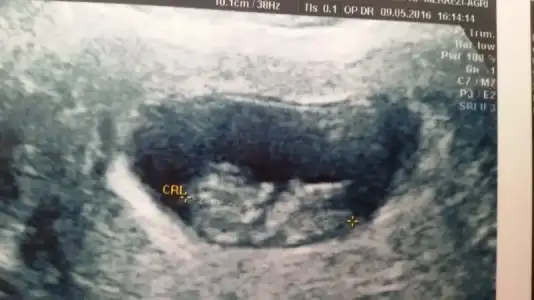

Bende yorum istiyorum :)) bunu yorumlayin sonra ilk çocuğumun ultrason kağıdını atcam :)

• _20160509_145824.webp

_20160509_145824.webp

16,6 KB · Görüntüleme: 120

Hep kasigimin sol tarafi agriyor bizde yorum alabilirmiyiz?

• image.webp

image.webp

9,5 KB · Görüntüleme: 118